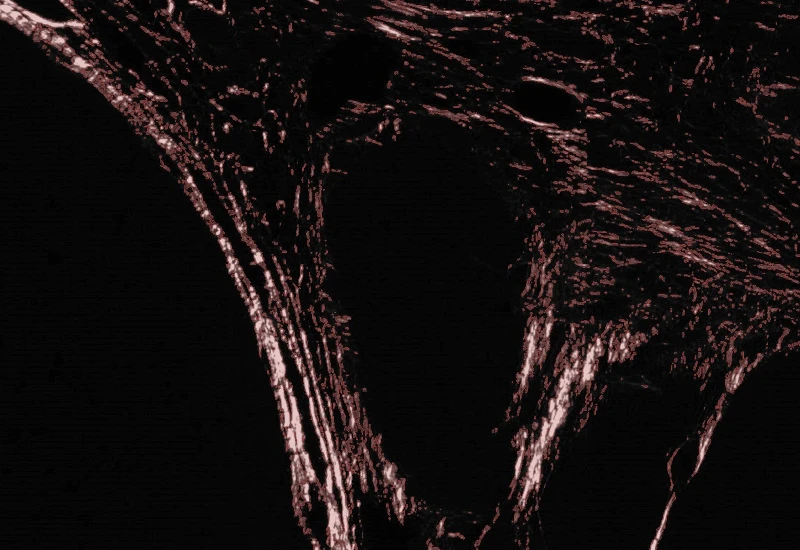

Sirius Red Polarized

Quantify collagen type I (red) and type III (green) fibers in Sirius Red–stained polarized images, measuring region area and the area of red, green, and overlapping (double-positive) fibers.

The Sirius Red Polarized App allows for quantification of collagen type I and type III based on Sirius Red Staining imaged with polarized light. It outputs the region area (µm2), the area of collagen type I = red fibres (µm2), collagen type III = green fibres (µm2) and overlapping fibres (µm2).

Image courtesy of Dr. Mortiz Uhlig, University Hospital RWTH Aachen

Detection of collagen type I

Detection of collagen type III

Overlapping of collagen type I and III